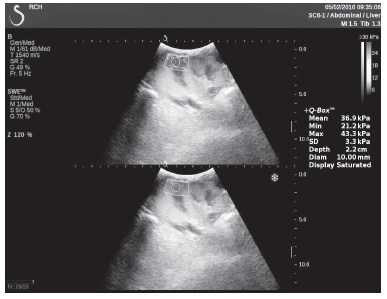

Клинический пример из первой группы. Пациент М., с хронической почечной недостаточностью. Трансплантация почки произведена от живого родственного донора. Трансплантат находится в правой подвздошной области. При нормальном функциональном состоянии трансплантата, показатели цветовой и спектральной допплерографии оценивались как удовлетворительные, с индексом резистентности не более 0,60 (рис. 1); показатели жесткости паренхимы почечного трансплантата при УЭСВ на различных участках составили от 20,05 до 29,18 кПа (рис. 2-4).

Рисунок 2. Исследование в режиме ультразвуковой эластографии сдвиговой волны у пациента М.: жесткость паренхимы в зоне медиального края трансплантата 19,8 кПа

Рисунок 7. Исследование в режиме ультразвуковой эластографии сдвиговой волны у пациента К.: жесткость паренхимы в зоне медиального края почечного трансплантата 36,9 кПа